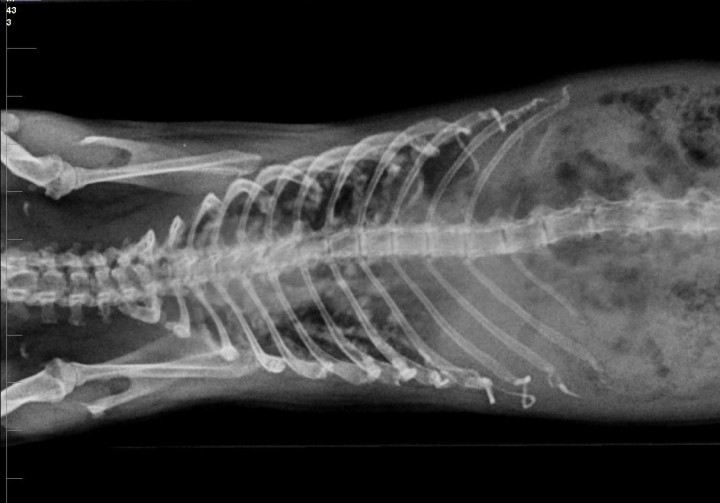

El paciente se recuperó adecuadamente, pero tres meses más tarde acudió a consulta con un cuadro agudo de disnea. En la exploración en consulta del animal se detectó disnea de tipo espiratorio y pérdida de peso (920 g). Se realizaron radiografías que mostraron un patrón nodular pulmonar con punteado difuso de densidad radiopaca, compatible con metástasis (Figs. 11 y 12). Los propietarios decidieron la eutanasia humanitaria del animal y no accedieron a la realización de necropsia.

<p>Radiografía de tórax. Proyección ventrodorsal. Se observa un patrón nodular difuso que ocupa todo el campo pulmonar, compatible con metástasis.</p>

Figura 12

Radiografía de tórax. Proyección ventrodorsal. Se observa un patrón nodular difuso que ocupa todo el campo pulmonar, compatible con metástasis.